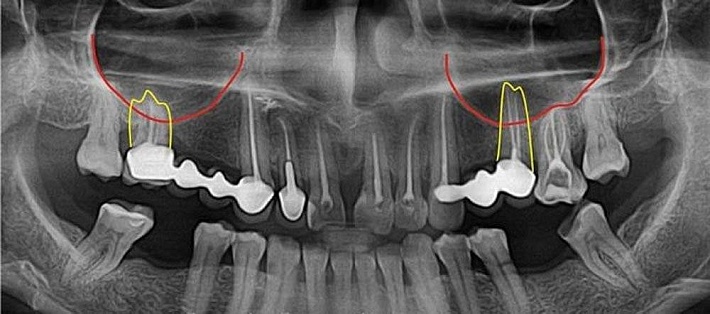

- Назначают пациенту рентгенографическое исследование гайморовых полостей и ортопантомографию;

Как уже упоминалось, риск появления перфорации гайморовой полости достаточно высок во время выполнения тех или иных процедур на верхней челюсти. Согласно медицинской статистике, почти в 5% случаев это происходит при экстрации зубов: чаще всего – у мужчин в возрасте от двадцати до сорока лет. Около 15% перфораций сопровождается попаданием фрагментов повреждённого зуба или материала, используемого для пломбирования.

- Особенности анатомического строения верхней челюсти и зубов (слишком длинные корни, их расположение в полости, недостаточный объём костной ткани);

- Особенности анатомического строения верхнечелюстных пазух (пневматический тип строения) или патологические состояния (в частности – гаймориты);

- Местные патологии, которые вызвают истончение ткани кости (воспаление тканей пародонта, гранулёматозные/кистозные образования вокруг корня зуба).

Пневматический тип строения пазух характеризуется тем, что их слизистая контактирует с зубными корнями или отделена от них тонкой пластиной. По этой причине даже минимально травматичные манипуляции эндодонта или хирурга приведут к необходимости проведения операции по закрытию перфорации верхнечелюстной пазухи. Она представляют собой дефект, давность которого не превышает двадцати дней. После этого ход покрывается эпителиальными тканями и формируется фистула.